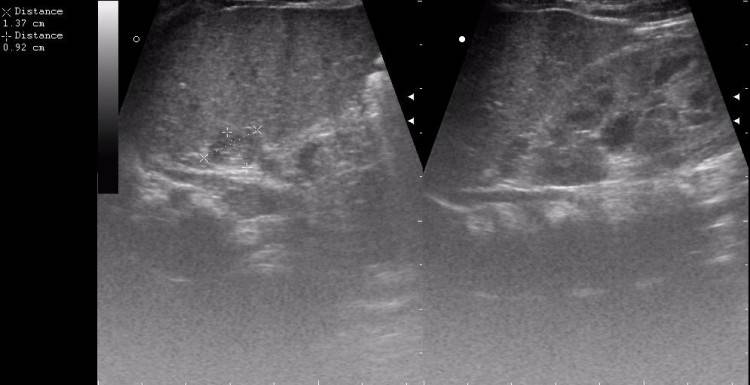

Что же показывает УЗИ надпочечников? Из исследования видно, что правый надпочечник размещен в пространстве верхнемедиальной поверхности правой почки и полой вены снизу. Его размеры:

- длина – 1-1,5 см.;

- ширина – 0,3-1,6 см.;

- высота – 1-2 см.

Левая железа помещена в зону левой почки и аорты. Размеры здорового надпочечника:

- длина – 1,5-2,5 см.;

- ширина – 0,8-1,5 см.;

- высота имеет приблизительно одинаковые характеристики с длиной.

Ультразвуковое исследование надпочечников проводится при большом разрешении. Размеры надпочечников могут варьировать.

- Длина около 1-1,5 см.

- Ширина – 0,25-1,7 см.

Размеры здорового левого надпочечника:

- Длина – 1,5-2,5 см.

- Ширина – 0,7-1,6 см.

- Высота равна длине.